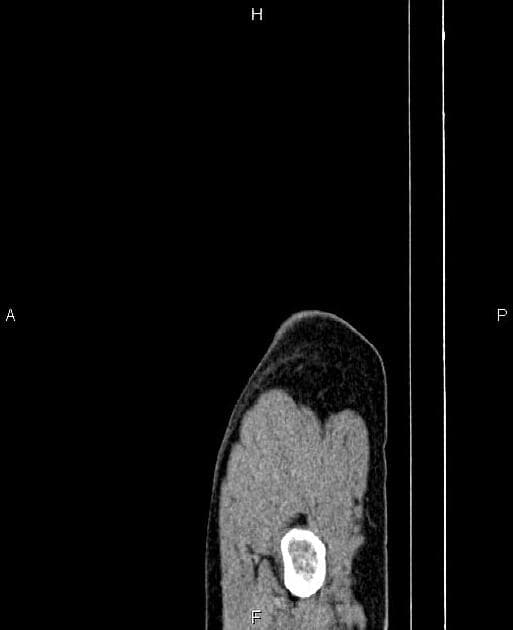

U nang ống mật chủ type III (Choledochocoele)

U nang ống mật chủ type III (Choledochocoele) trên hình ảnh chụp đường mật trong mổ và CT.

- Giãn ống mật chủ ngoài gan trong thành tá tràng, trong lòng có sỏi.

- "Choledochocoele là dạng hiếm của u nang ống mật chủ type III, đặc trưng bởi giãn dạng nang đoạn ống mật chủ trong thành tá tràng."

- "Chẩn đoán xác định bằng các phương tiện hình ảnh như MRCP hoặc chụp đường mật nội soi, điều trị triệt để là cắt bỏ hoàn toàn để ngăn ngừa ác tính hóa."